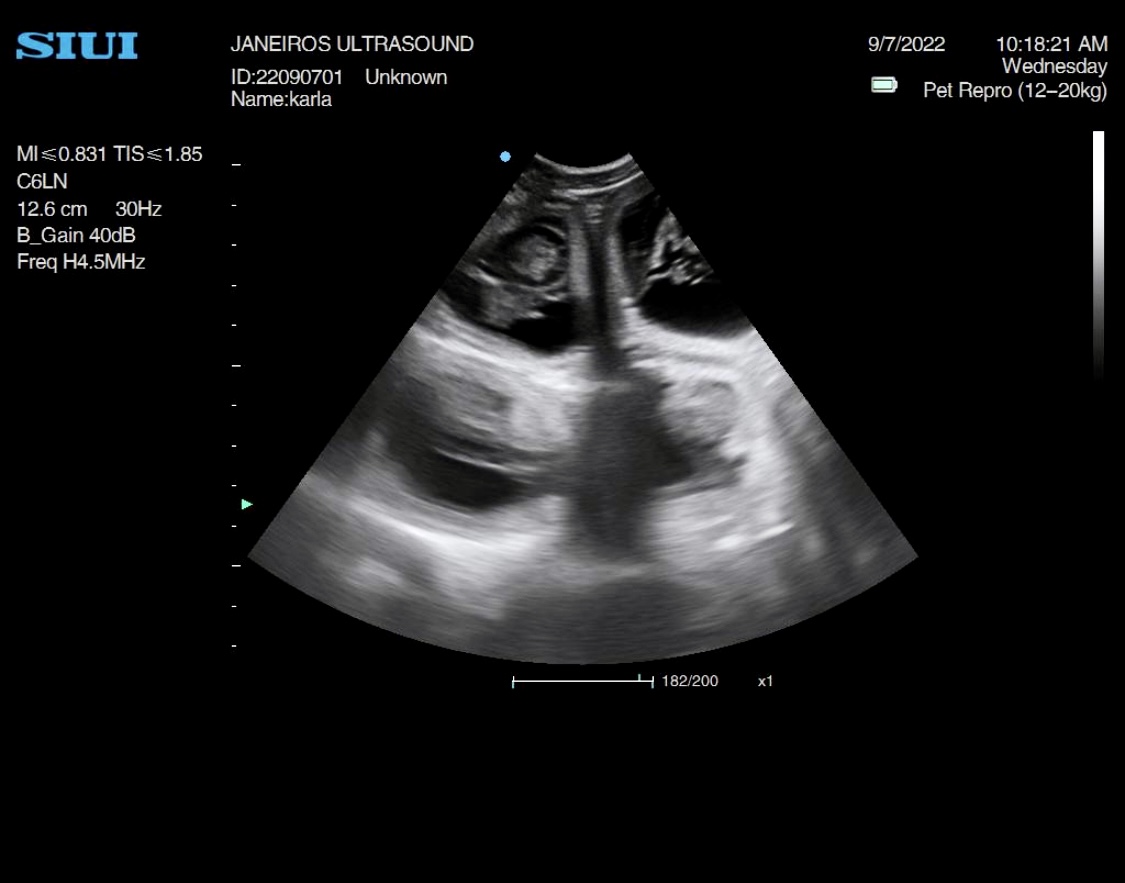

This stunning girl I scanned this morning. She was quite hyper so it was a task getting her to keep still. she has quite a few babies in there I counted at least 10!!

UPDATE….The puppies have arrived and all 10 are doing well 😊 pictures below.